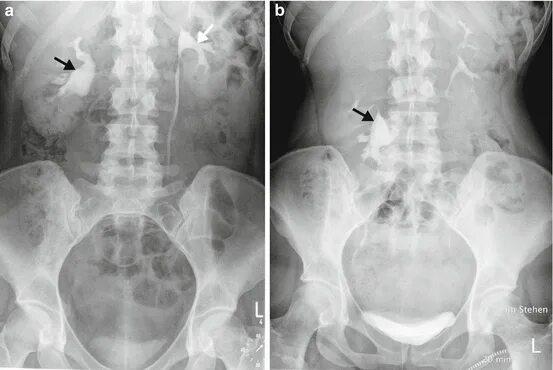

Нефроптоз почки слева